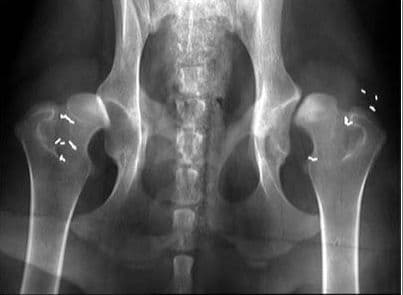

Sau khi khám lâm sàng, bác sĩ có thể yêu cầu người bệnh chụp X-quang nhằm tìm kiếm nguyên nhân gây đau nhức, khó chịu. Nếu bệnh nhân bị thoái hóa khớp háng, chụp X-quang sẽ cho ra kết quả:

– Khe khớp hẹp do lớp sụn khớp đã bị bào mòn

– Gai xương phát triển tại nhiều vị trí, bao gồm chỏm xương đùi và xương chậu

– Đặc xương dưới sụn ở vùng chịu áp lực tỳ đè lớn

– Khuyết xương